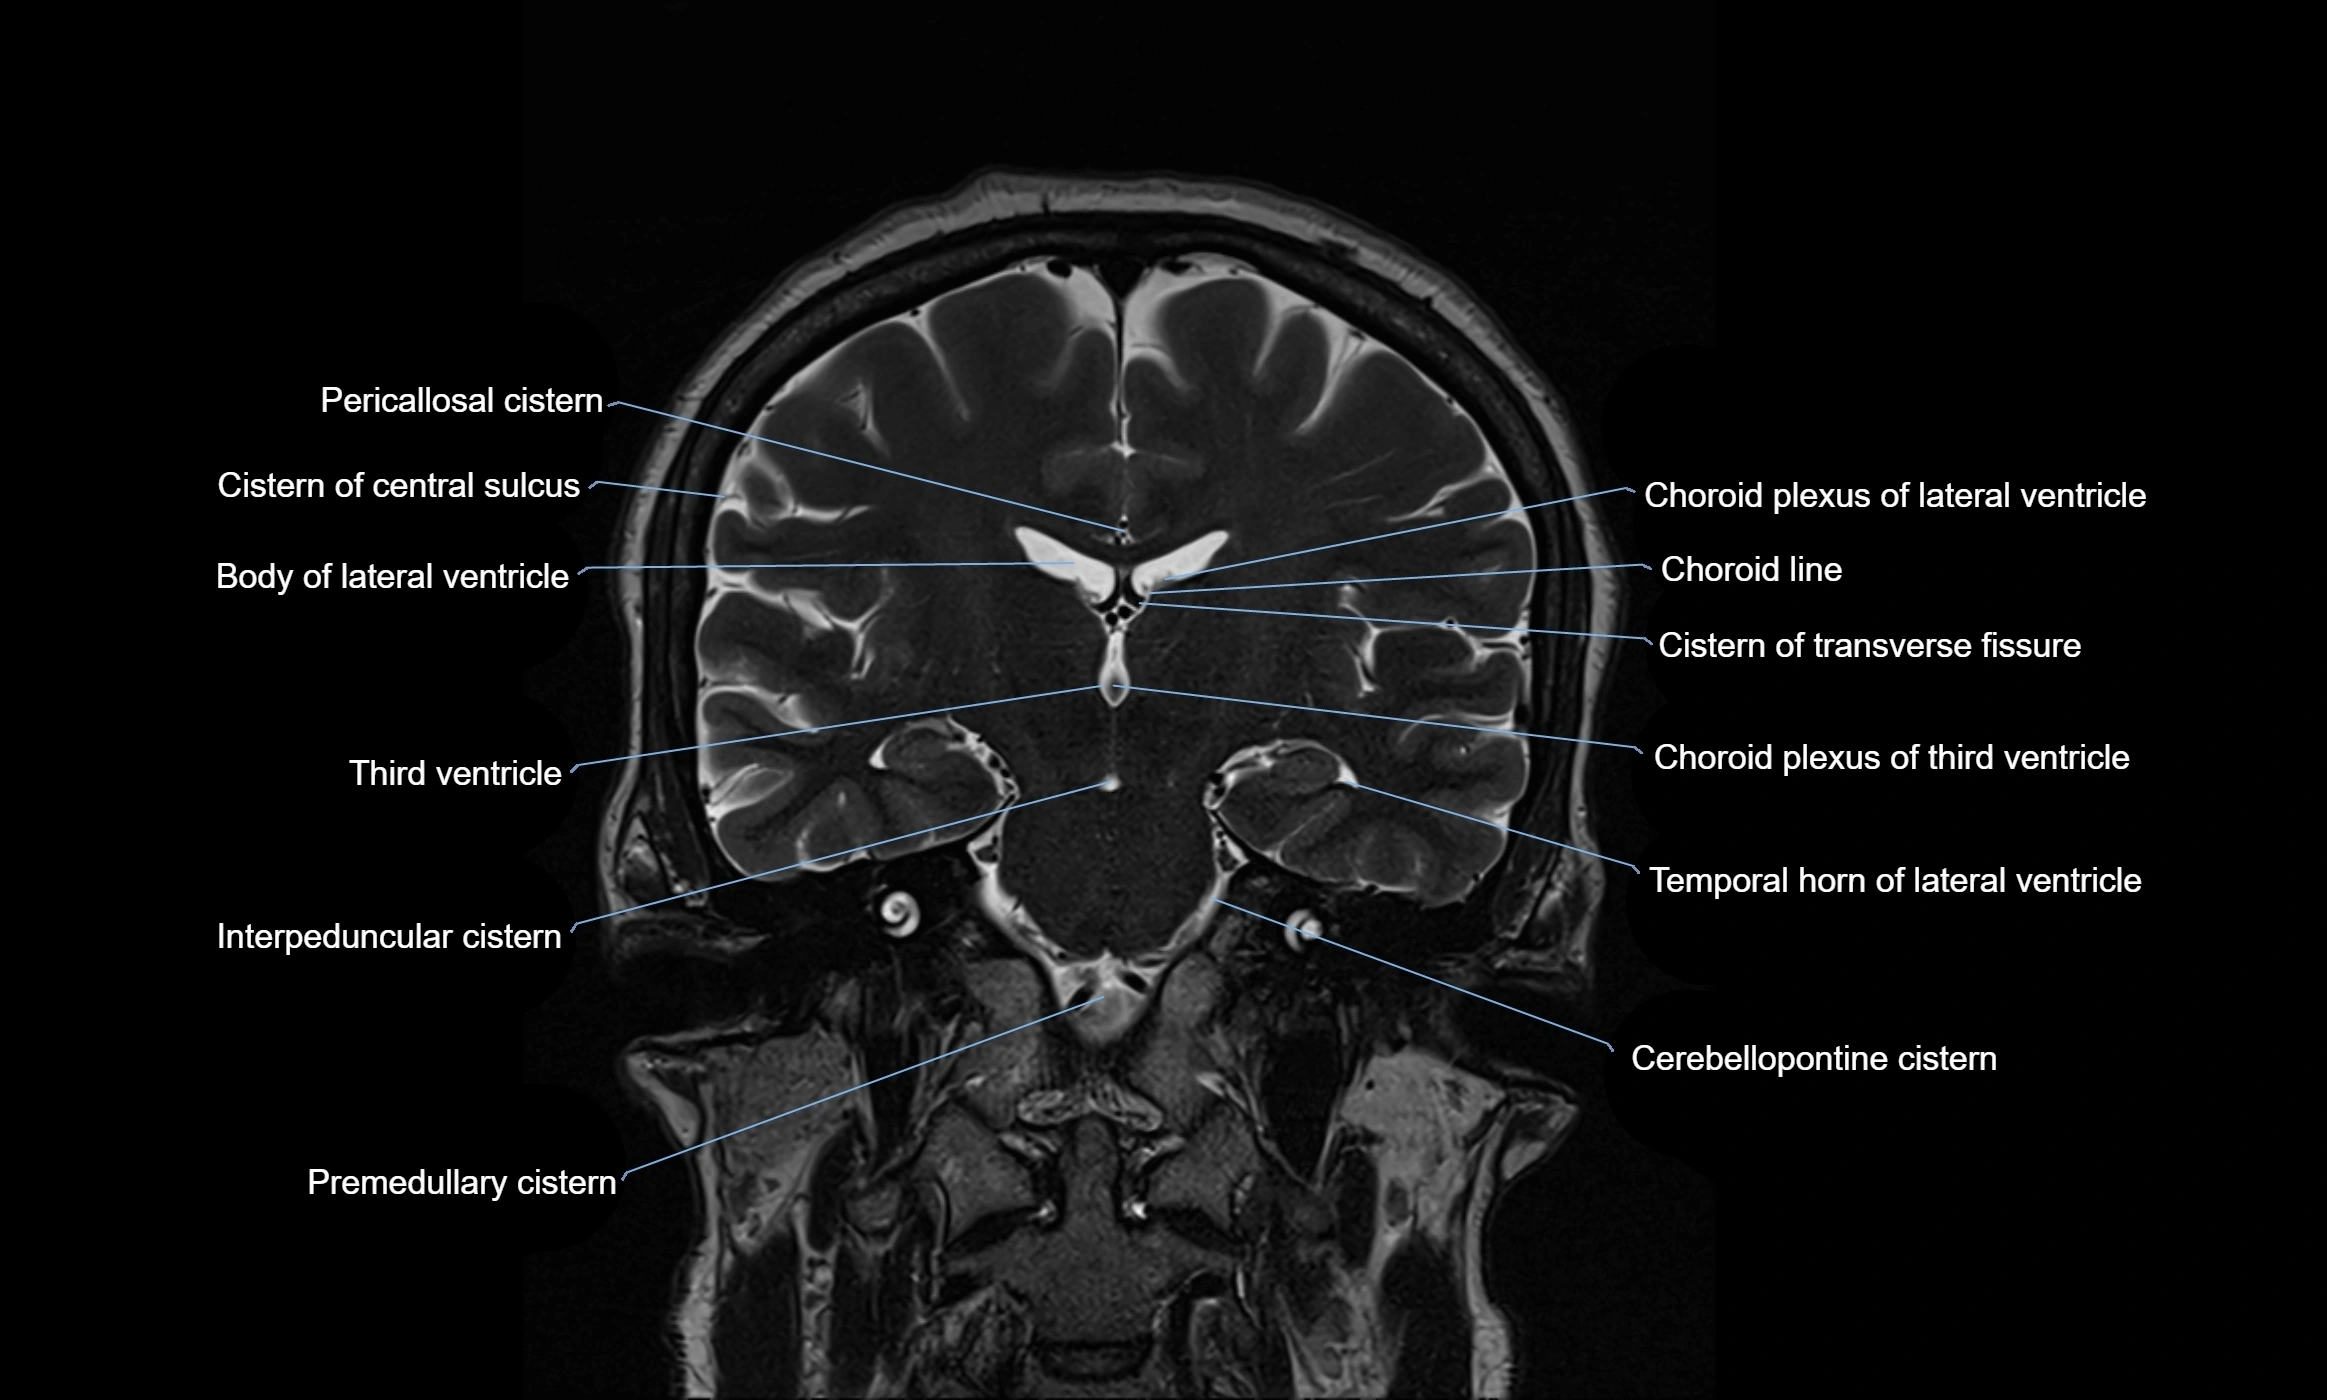

Ambient cistern

The ambient cistern is a paired, narrow, and elongated subarachnoid space located bilaterally along the lateral aspect of the midbrain. It serves as a conduit between the interpeduncular cistern anteriorly and the quadrigeminal cistern posteriorly. This cistern houses critical neurovascular structures, including parts of the posterior cerebral artery, superior cerebellar artery, trochlear nerve (cranial nerve IV), and the basal vein of Rosenthal. It plays an important role in the circulation of cerebrospinal fluid (CSF) and provides an anatomical corridor for various vessels and nerves passing around the midbrain.

MRI Appearance

• T2-weighted images:

• The cistern is hyperintense (bright) due to the high water content of CSF.

• Encapsulated vessels and nerves are seen as flow voids or hypointense lines within the bright background.

MRI images

image